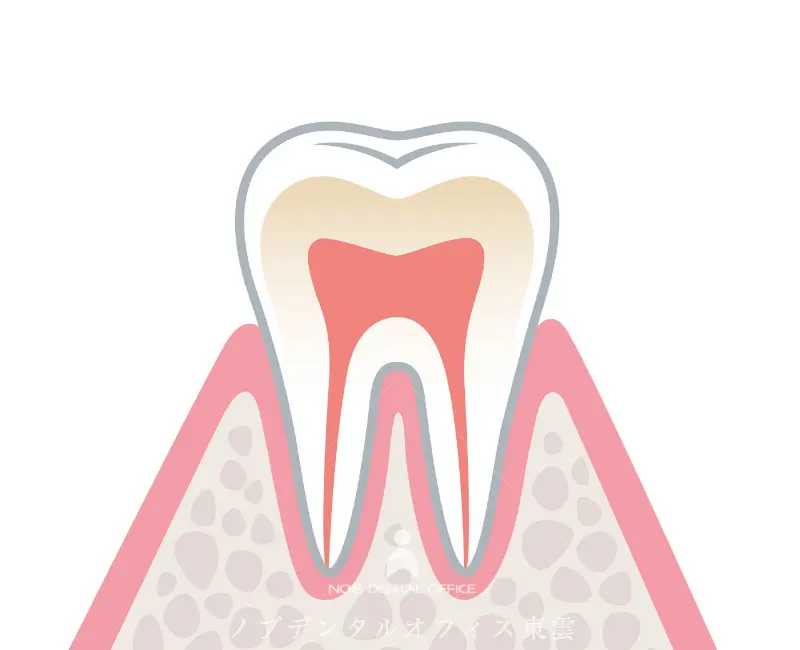

歯肉炎(初期段階)

プラーク(細菌のかたまり)が歯ぐきの周りにたまることで炎症が起き、歯ぐきが赤く腫れたり、ブラッシングやフロスで出血しやすくなります。

この歯肉炎の段階では まだ骨の破壊はなく、適切な治療とケアで元の状態に戻ることが期待できます。

軽度〜中等度歯周炎

(初期の歯周病)

※歯ぐきが下がったなどの自覚症状

炎症が歯ぐきの奥へ進み、歯ぐきが下がりはじめ、歯と歯ぐきの間に 4mm以上の歯周ポケット」ができ始めます。

歯を支える骨も一部失われていきます。

治療により進行を抑えることは可能ですが、一度失われた骨が完全に元に戻ることは難しい場合があります。